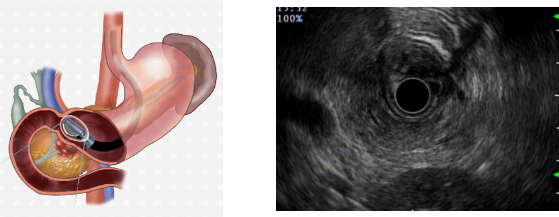

-초음파내시경(EUS)

:: 내시경 끝에 초음파 변환기를 부착하여 위나 십이지장을 통해서 초음파를 이용하여 췌장을 검사 :: 필요한 경우 종양에 대한 조직검사도 가능